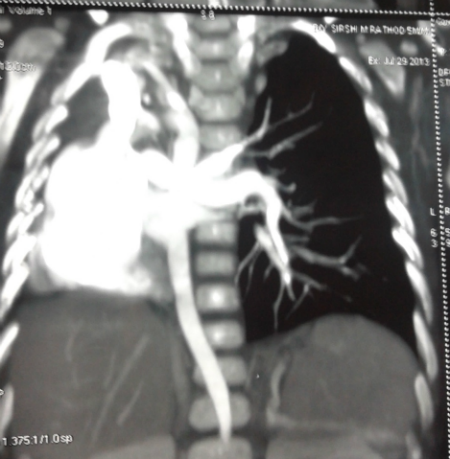

A 3-day old female neonate born at full term through normal vaginal delivery presented with had absent anal opening; she was passing stool from vestibule. The antenatal period was uneventful, but there was no record of ANC or antenatal ultrasonography. Local examination revealed presence of persistent cloaca. There was no palpable abdominal lump. Her respiratory rate was normal and she was maintaining adequate saturation on air. On auscultation, breath sounds were absent on right side. The chest x-ray reveled opacification of the right hemi thorax with mediastinal shift. In view of her stable cardio- respiratory status, we decided to first do a transverse colostomy for fecal diversion before further investigation for her lung condition. The perioperative course was uneventful. Postoperatively the baby was investigated for right hemithorax opacification. She underwent 2D- Echocardiogram which showed absent right pulmonary artery, tiny PDA, small ASD. Patient was discharged on 5th postoperative day on oral feeds with healthy functioning stoma. She was put on distal loop washouts and observation. Her cardio-respiratory status continued to be stable. On follow-up at 6 months age, CT angiography chest was done which was suggestive of agenesis of right pulmonary artery and pulmonary vein, right pulmonary agenesis and aberrant right subclavian artery (Fig. 1). We did a diagnostic bronchoscopy that revealed complete absence of right main bronchus and trachea continued as a single left bronchus with normal distal branching confirming the diagnosis of right lung agenesis. Since patient is asymptomatic, no intervention has been done for her lung condition. She is now waiting for definitive surgery for cloaca.

Figure 1: CT angiogram